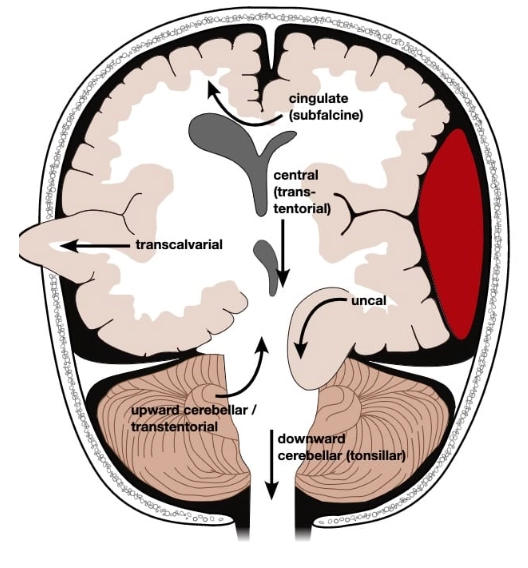

Thoát vị não (Brain herniation)

Thoát vị dưới liềm (Subfalcine Herniation - SFH)

Thoát vị móc hải mã (Uncal Herniation)- Thoát vị xuyên lều xuống dưới một bên (Unilateral Descending Transtentorial Herniation)

Thoát vị trung tâm (Central Herniation)-Thoát vị xuyên lều xuống dưới hai bên (Bilateral Descending Transtentorial Herniation)

Thoát vị lều tiểu não hướng lên (Ascending Transtentorial Herniation)

Thoát vị hạnh nhân tiểu não (Tonsillar Herniation)

Thoát vị não ra ngoài sọ (Extracranial Brain Herniation)